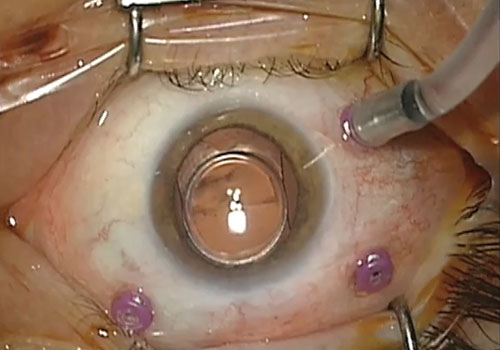

La vitrectomia invece consiste nell’appianare la retina non dall’esterno ma dall’interno con dei sistemi mini invasivi. La vitrectomia è eseguita per mezzo di uno strumento (vitrectomo) che taglia e aspira il corpo vitreo. Il vitrectomo viene introdotto nell’occhio attraverso una piccola apertura nella sclera, la parte bianca dell’occhio. Insieme al vitrectomo sono necessari, una fibra ottica per illuminare la cavità oculare ed un cannello d’infusione per sostituire il liquido vitreale asportato dal vitrectomo, mantenendo costante la pressione endo-oculare. Questi strumenti accessori sono inseriti in altrettante aperture della sclera.

Tanto più piccole sono queste aperture, meno invasivo è l’intervento per l’occhio del paziente. A fine intervento vengono molto spesso lasciate delle sostanze tamponanti (gas, olio di silicone, aria) per facilitare l’appianamento della retina.